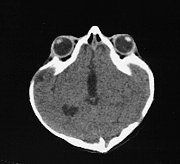

Crouzon Syndrome

• most common syndrome

• involves sagittal and coronal sutures

• shallow orbits, proptosis

• hypertelorism

• midface hypoplasia

• often, hydrocephalus